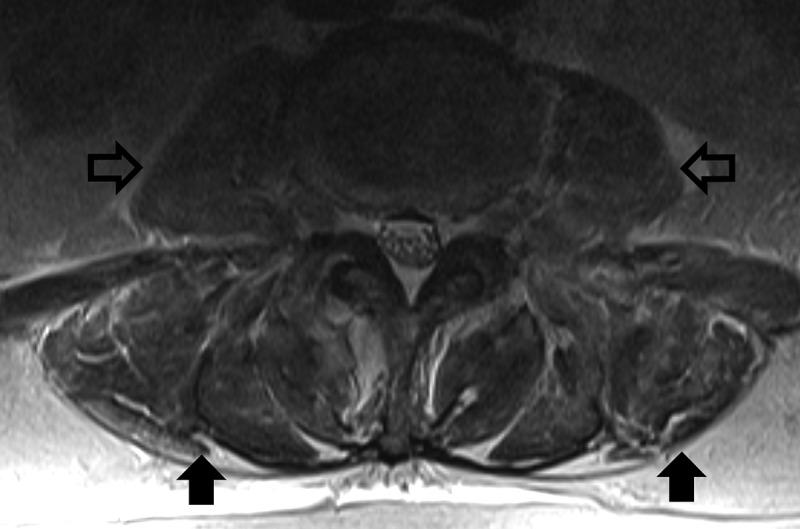

Dermatomyositis (DM) and polymyositis (PM) are both immune-mediated inflammatory myopathies known to occur in paraneoplastic syndromes associated with a new diagnosis of malignancy, most commonly breast, ovarian, lung, pancreatic, stomach, colorectal, and Non-Hodgkin's lymphoma in DM and breast, lung, bladder cancer, and Non-Hodgkin's lymphoma in PM. While inflammatory markers such as creatine kinase (CK) may be elevated with either DM or PM, marked elevation is rare. Herein, we report a case of newly diagnosed pancreatic cancer presenting with inflammatory myopathy and marked CK elevation. We review the frequency of PM as a paraneoplastic syndrome, the association with marked CK elevation, and the association with pancreatic cancer.

皮肌炎(DM)和多发性肌炎(PM)均为免疫介导的炎性肌病,已知可发生于与新诊断恶性肿瘤相关的副肿瘤综合征中,在皮肌炎中最常见于乳腺癌、卵巢癌、肺癌、胰腺癌、胃癌、结直肠癌和非霍奇金淋巴瘤,在多发性肌炎中最常见于乳腺癌、肺癌、膀胱癌和非霍奇金淋巴瘤。虽然肌酸激酶(CK)等炎症标志物在皮肌炎或多发性肌炎中可能升高,但显著升高较为罕见。在此,我们报告一例新诊断的胰腺癌患者,其表现为炎性肌病且肌酸激酶显著升高。我们回顾了多发性肌炎作为副肿瘤综合征的发生率、与肌酸激酶显著升高的关联以及与胰腺癌的关联。